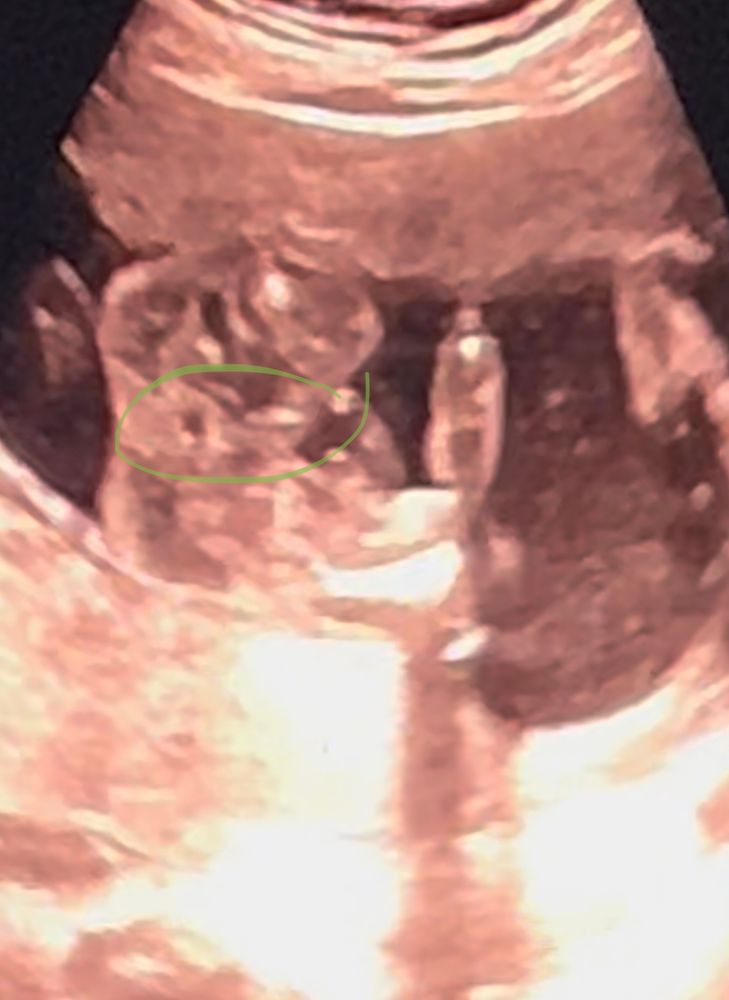

Пол малышаДевочки, знатоки)) Это ведь и есть то самое зернышко , про которое все говорят?))

Фото между ножек , со стороны попы ))

Лучший ответ

Кошка В Сапожках

Да, кофейное зернышко 🤗🤗🤗